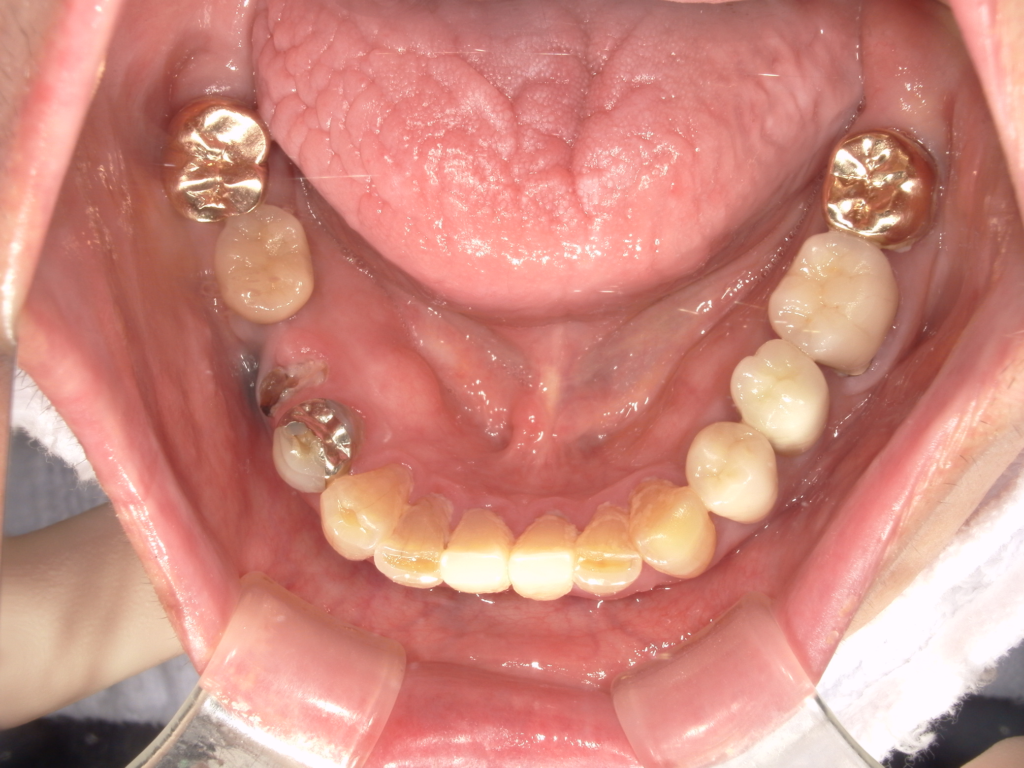

Y様インプラント実例 #44

左の上下の奥歯をインプラントで治療しています。

左下の奥歯は歯を抜くのと同時にインプラントの埋め込みを行っています。

被せものは上下、セラミックスで作っています。

治療前

治療後